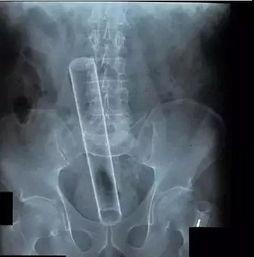

首先,让我们来认识一下这个神秘的小物件。肛尾塞,顾名思义,就是塞入肛门尾部的塞子。它通常由硅胶、橡胶等材质制成,形状多样,有圆柱形、锥形、花瓣形等。别看它小,作用可大着呢!